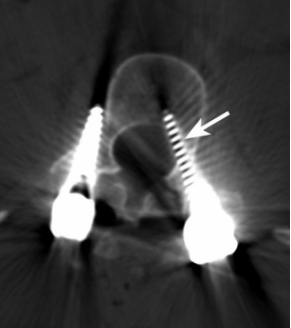

3 CT显示螺钉移位

植入物相关并发症包括植入物松动、移位、拔出或断裂等,可能导致血管、神经和脏器损伤。Weiss等综述性研究认为螺钉移位是微创经椎间孔腰椎融合术常见并发症之一。Liu等通过对3936例腰椎手术患者的临床资料进行分析,发现21例因螺钉移位再次手术。Ghobrial等的系统综述显示,在2052例患者中有37例在腰椎后路减压融合术后发生神经功能损伤,其中11例是螺钉移位造成。Khalifa等研究纳入51例接受腰椎融合术的患者,平均随访24个月,发现1例因螺钉移位而再次手术。Šámal等发现,51例腰椎间盘退变患者行微创腰椎后路椎间融合术后,发生5例螺钉移位,1例再次手术调整植入物。Tsai等统计分析了10350例多种脊柱手术患者临床资料,发现4 984例螺钉植入患者中有41例术后1周内发生螺钉移位,其中11例手术调整螺钉,余30例拔除螺钉后未重新植入。除螺钉移位需要再次手术治疗外,骨水泥外渗的患者必要时也需要采取手术治疗。Janssen等报道165例接受胸腰椎骨水泥增强椎弓根螺钉手术的脊柱肿瘤或脊柱退行性疾病患者中,有10例发生骨水泥硬膜外渗漏,其中2例需要再次手术。螺钉和骨水泥等植入物是否稳定与骨质有很大的关系。Lee等提出骨质疏松症患者脊柱融合手术后更容易发生植入物并发症。Khalid等也提到,接受腰椎融合术的骨质疏松症或骨质减少患者术后并发症发生率较高,包括椎弓根螺钉松动等,部分患者需要再次接受手术治疗。植入物并发症一般发生在脊柱手术后较长时间,可能由于患者活动不当造成。因此,手术后应详细告知患者避免不当的活动方式,对于骨质疏松的患者更应提高警惕,术后帮助患者改善骨质,减少再次手术风险。